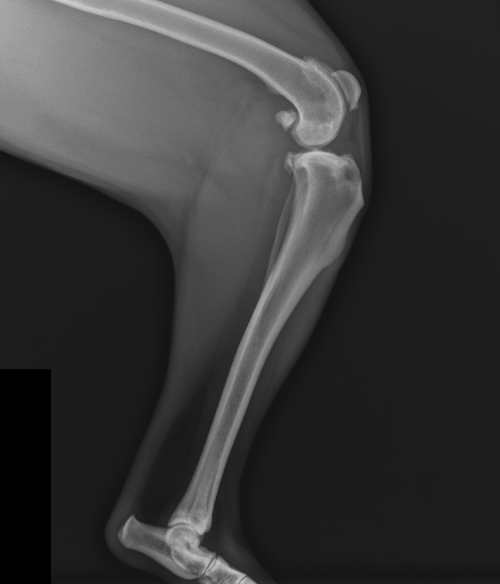

Při rentgenologickém vyšetření zhotovujeme dvě projekce – předozadní a boční. Na snímku bychom měli zachytit distální polovinu femuru a proximální polovinu tibie. Pro zjištění sklonu TPA budeme potřebovat snímek, na němž bude současně i tarzus (11).

Obrázek 10: Kolenní kloub postižený rupturou LCC, obrázek vlastní

Začínáme s posouzením měkkých tkáních, kde se v případě ruptury vazu objevují i sekundární příznaky, jako například kloubní efúze nebo tvorba osteofytů (11). Tyto příznaky také představují výskyt osteoartritidy. Specifickými známkami chronické ruptury LCC je zbytnění měkkých tkání. V některých případech můžeme pozorovat kalcifikaci zbytků LCC (28).

Snímek posuzujeme i z důvodu, abychom případně odlišili i jiné příčiny kulhání (13). Rentgenologickým vyšetřením můžeme přijít také na patologické procesy, jimiž může být kostní tumor (11).